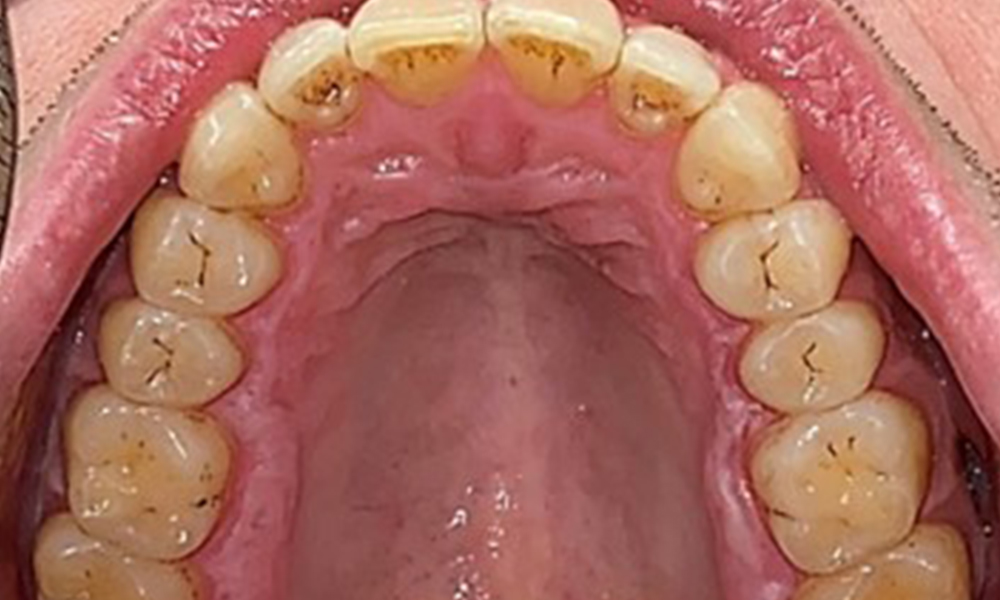

Occlusal view of the maxilla.

Fig. 3: Occlusal view of the maxilla, © Dr R. Krapf

Extraoral and intraoral findings

There were no pathological extraoral findings. During intraoral examination, inspection of the frontal view revealed brownish discolouration near the keratinised gingiva and at the transition to the moveable mucosa (Fig. 2), which could be attributed to nicotine consumption. Whitish mucosal lesions were observed on the palate, particularly near the maxillary molar palatal surfaces, indicating increased keratinisation and can also be attributed to nicotine consumption. The tongue was covered with a removable white and brownish coating.

The patient has full dentition with a total of 28 teeth. There were noteworthy erosions and attritions. (Fig. 4, Fig. 5). Due to bruxism, the patient has been wearing a splint with an adjusted bite block at night for many years. The erosions were caused by long-term consumption of isotonic beverages. No periodontal bone loss or active caries were observed.